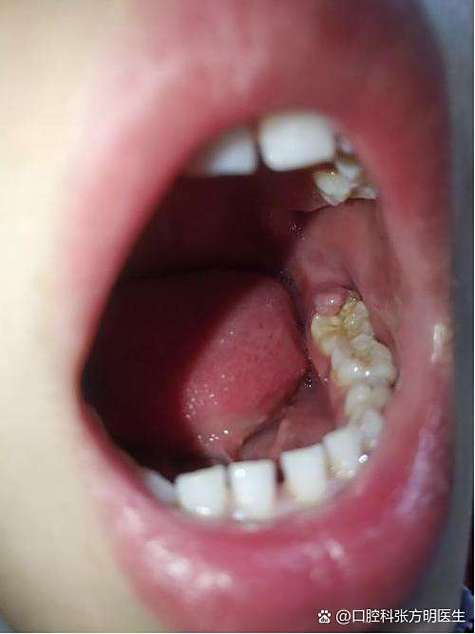

(图片来源网络,侵删)- 蛀牙(龋齿):倾斜生长的智齿与邻牙之间形成一个很难清洁的缝隙,食物嵌塞后,牙刷刷不到,极易导致邻牙蛀坏,甚至可能需要拔掉邻牙,非常可惜。